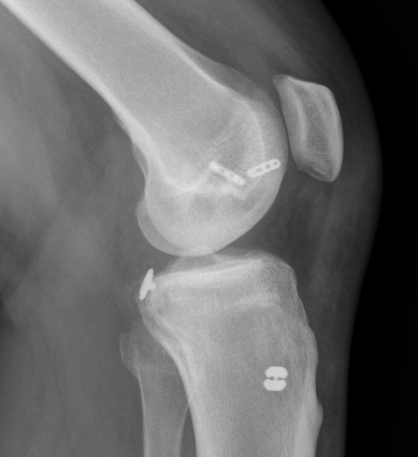

Acute femoral peel off of PCL

Acute Surgical Options

1. Repair bony avulsion

2. Acute suture repair of femoral peel off +/- augmentation

Acute repair of femoral peel off with suture tape augmentation

Indication

Femoral avulsion of the PCL

Acute injury

Technique

Repair to PCL to femoral insertion with sutures

Pass suture tape through tibial insertion to femoral insertion PCL to augment